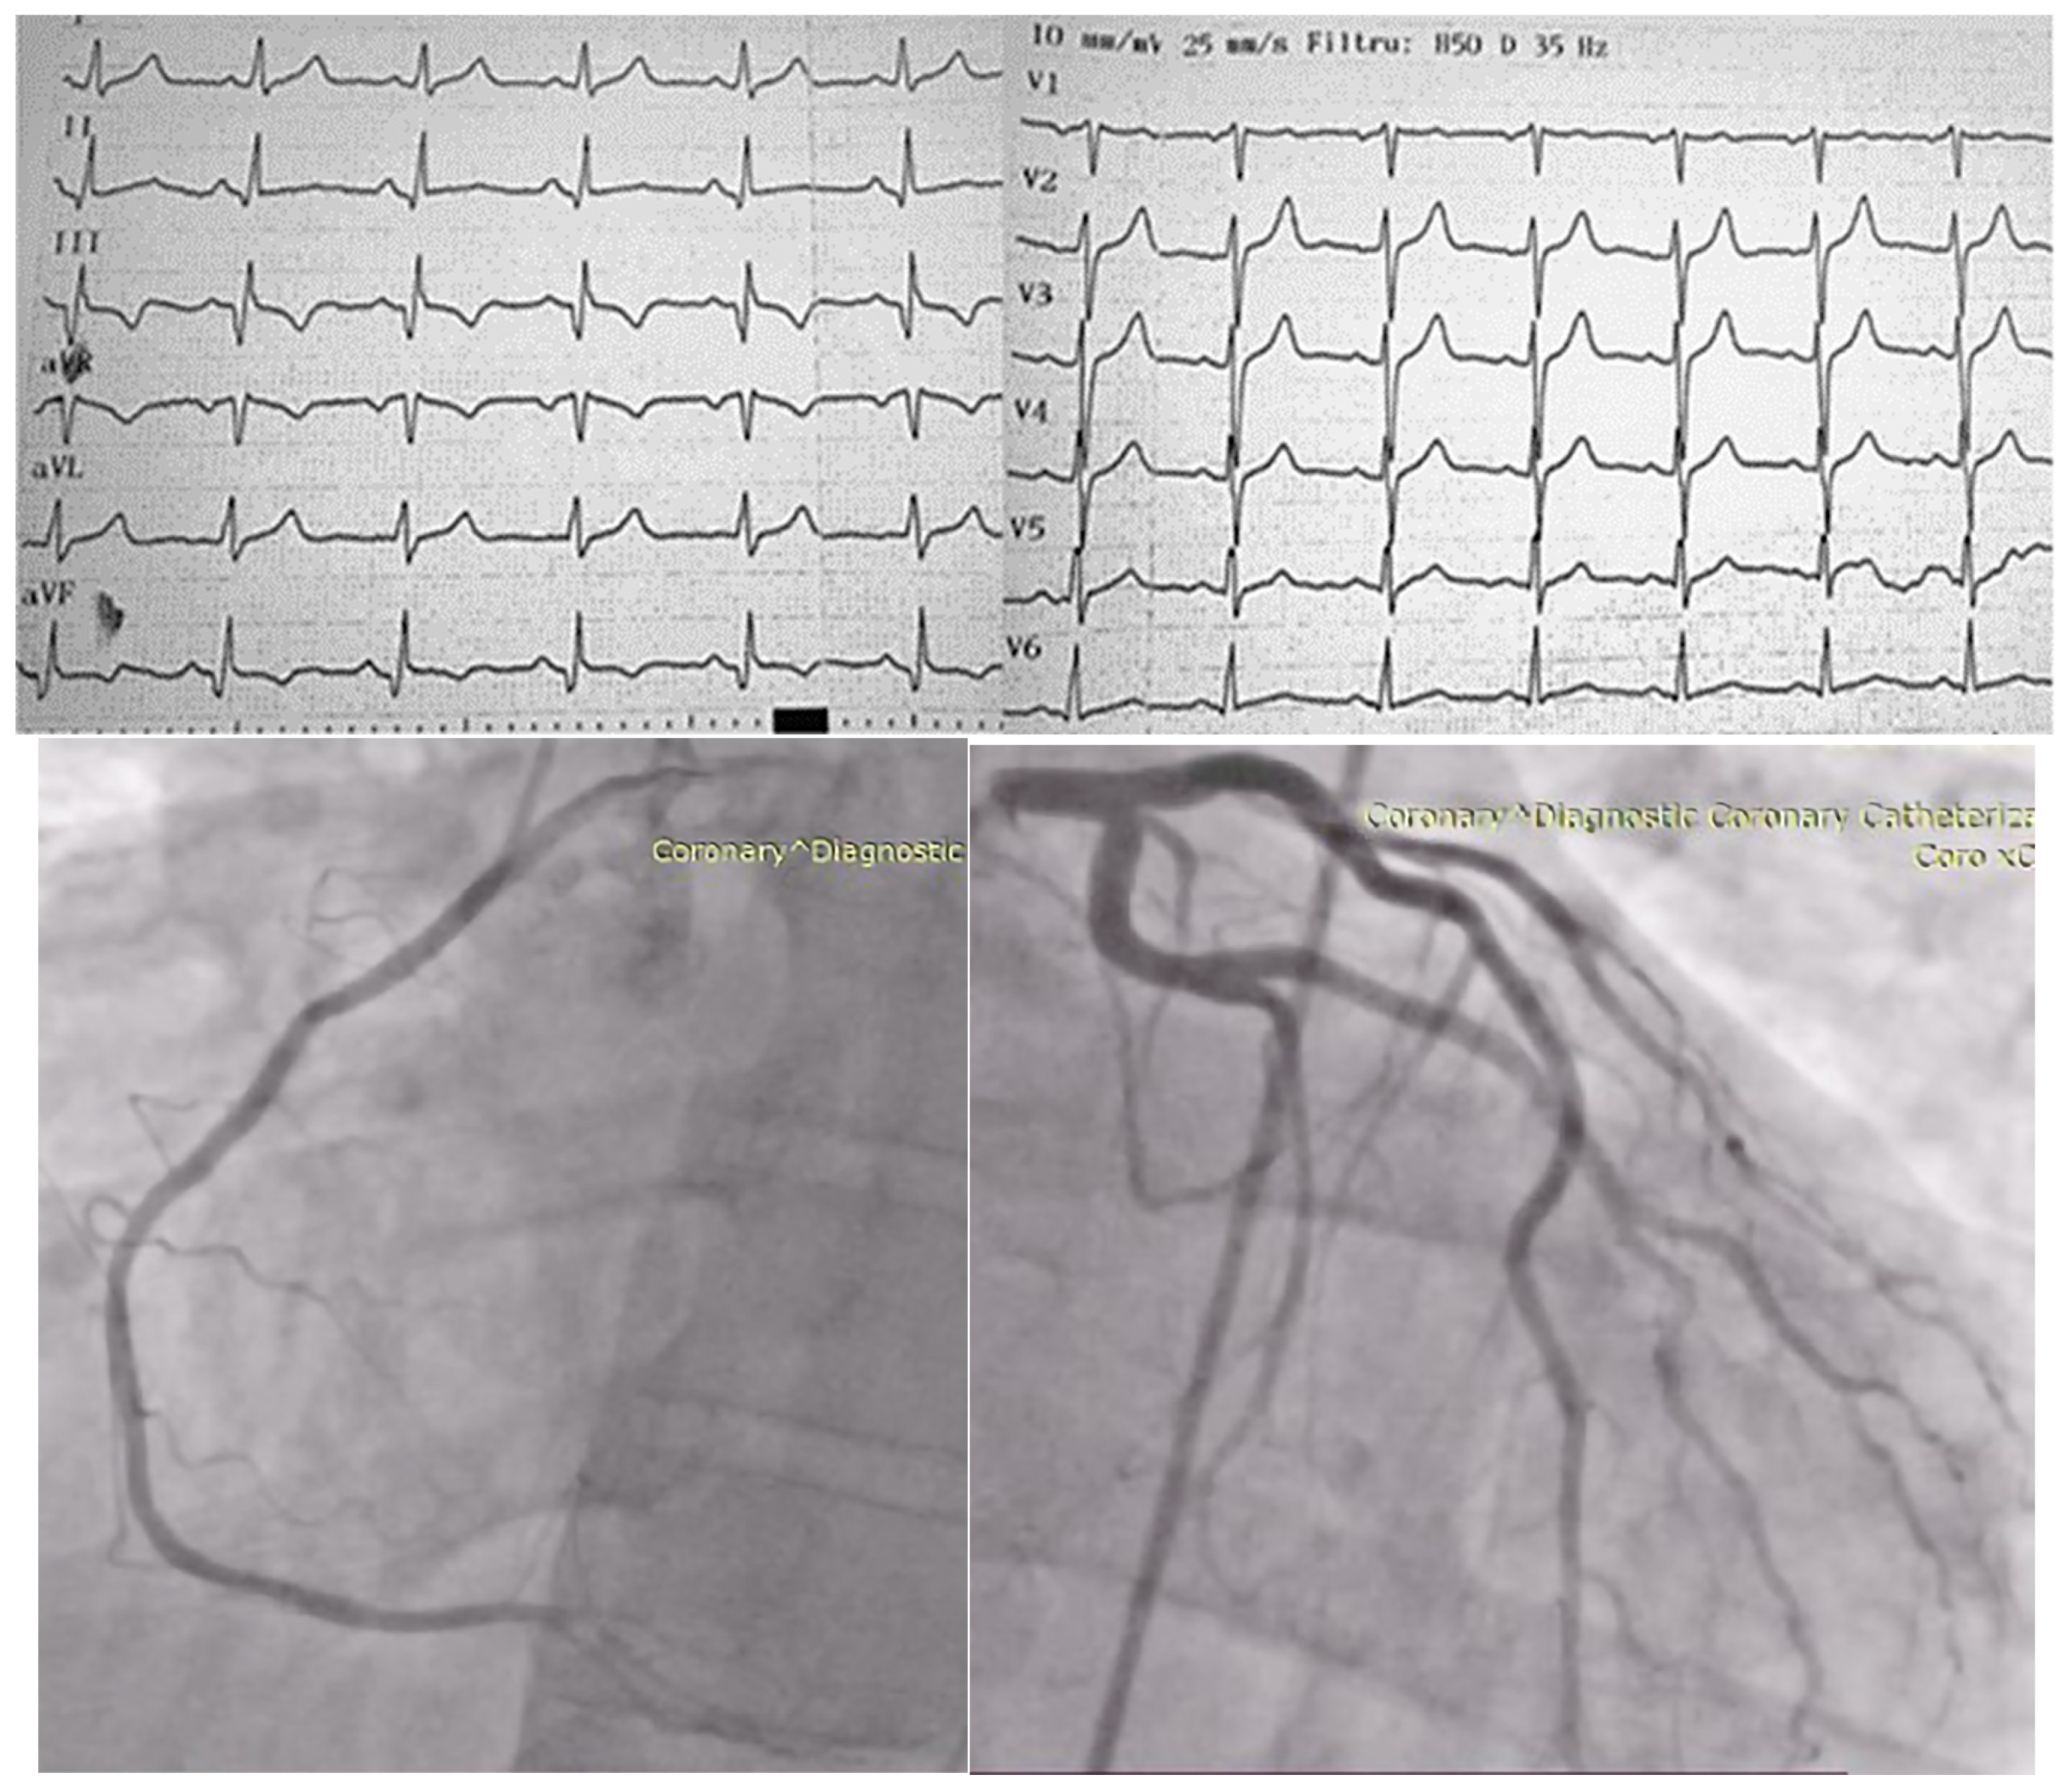

Particularities of a Cardiac Amorphous Left Ventricular Tumor in a Patient with Coronary Artery Disease—Diagnostic and Therapeutic Challenges: A Case Report and Literature Review

2. Case Presentation